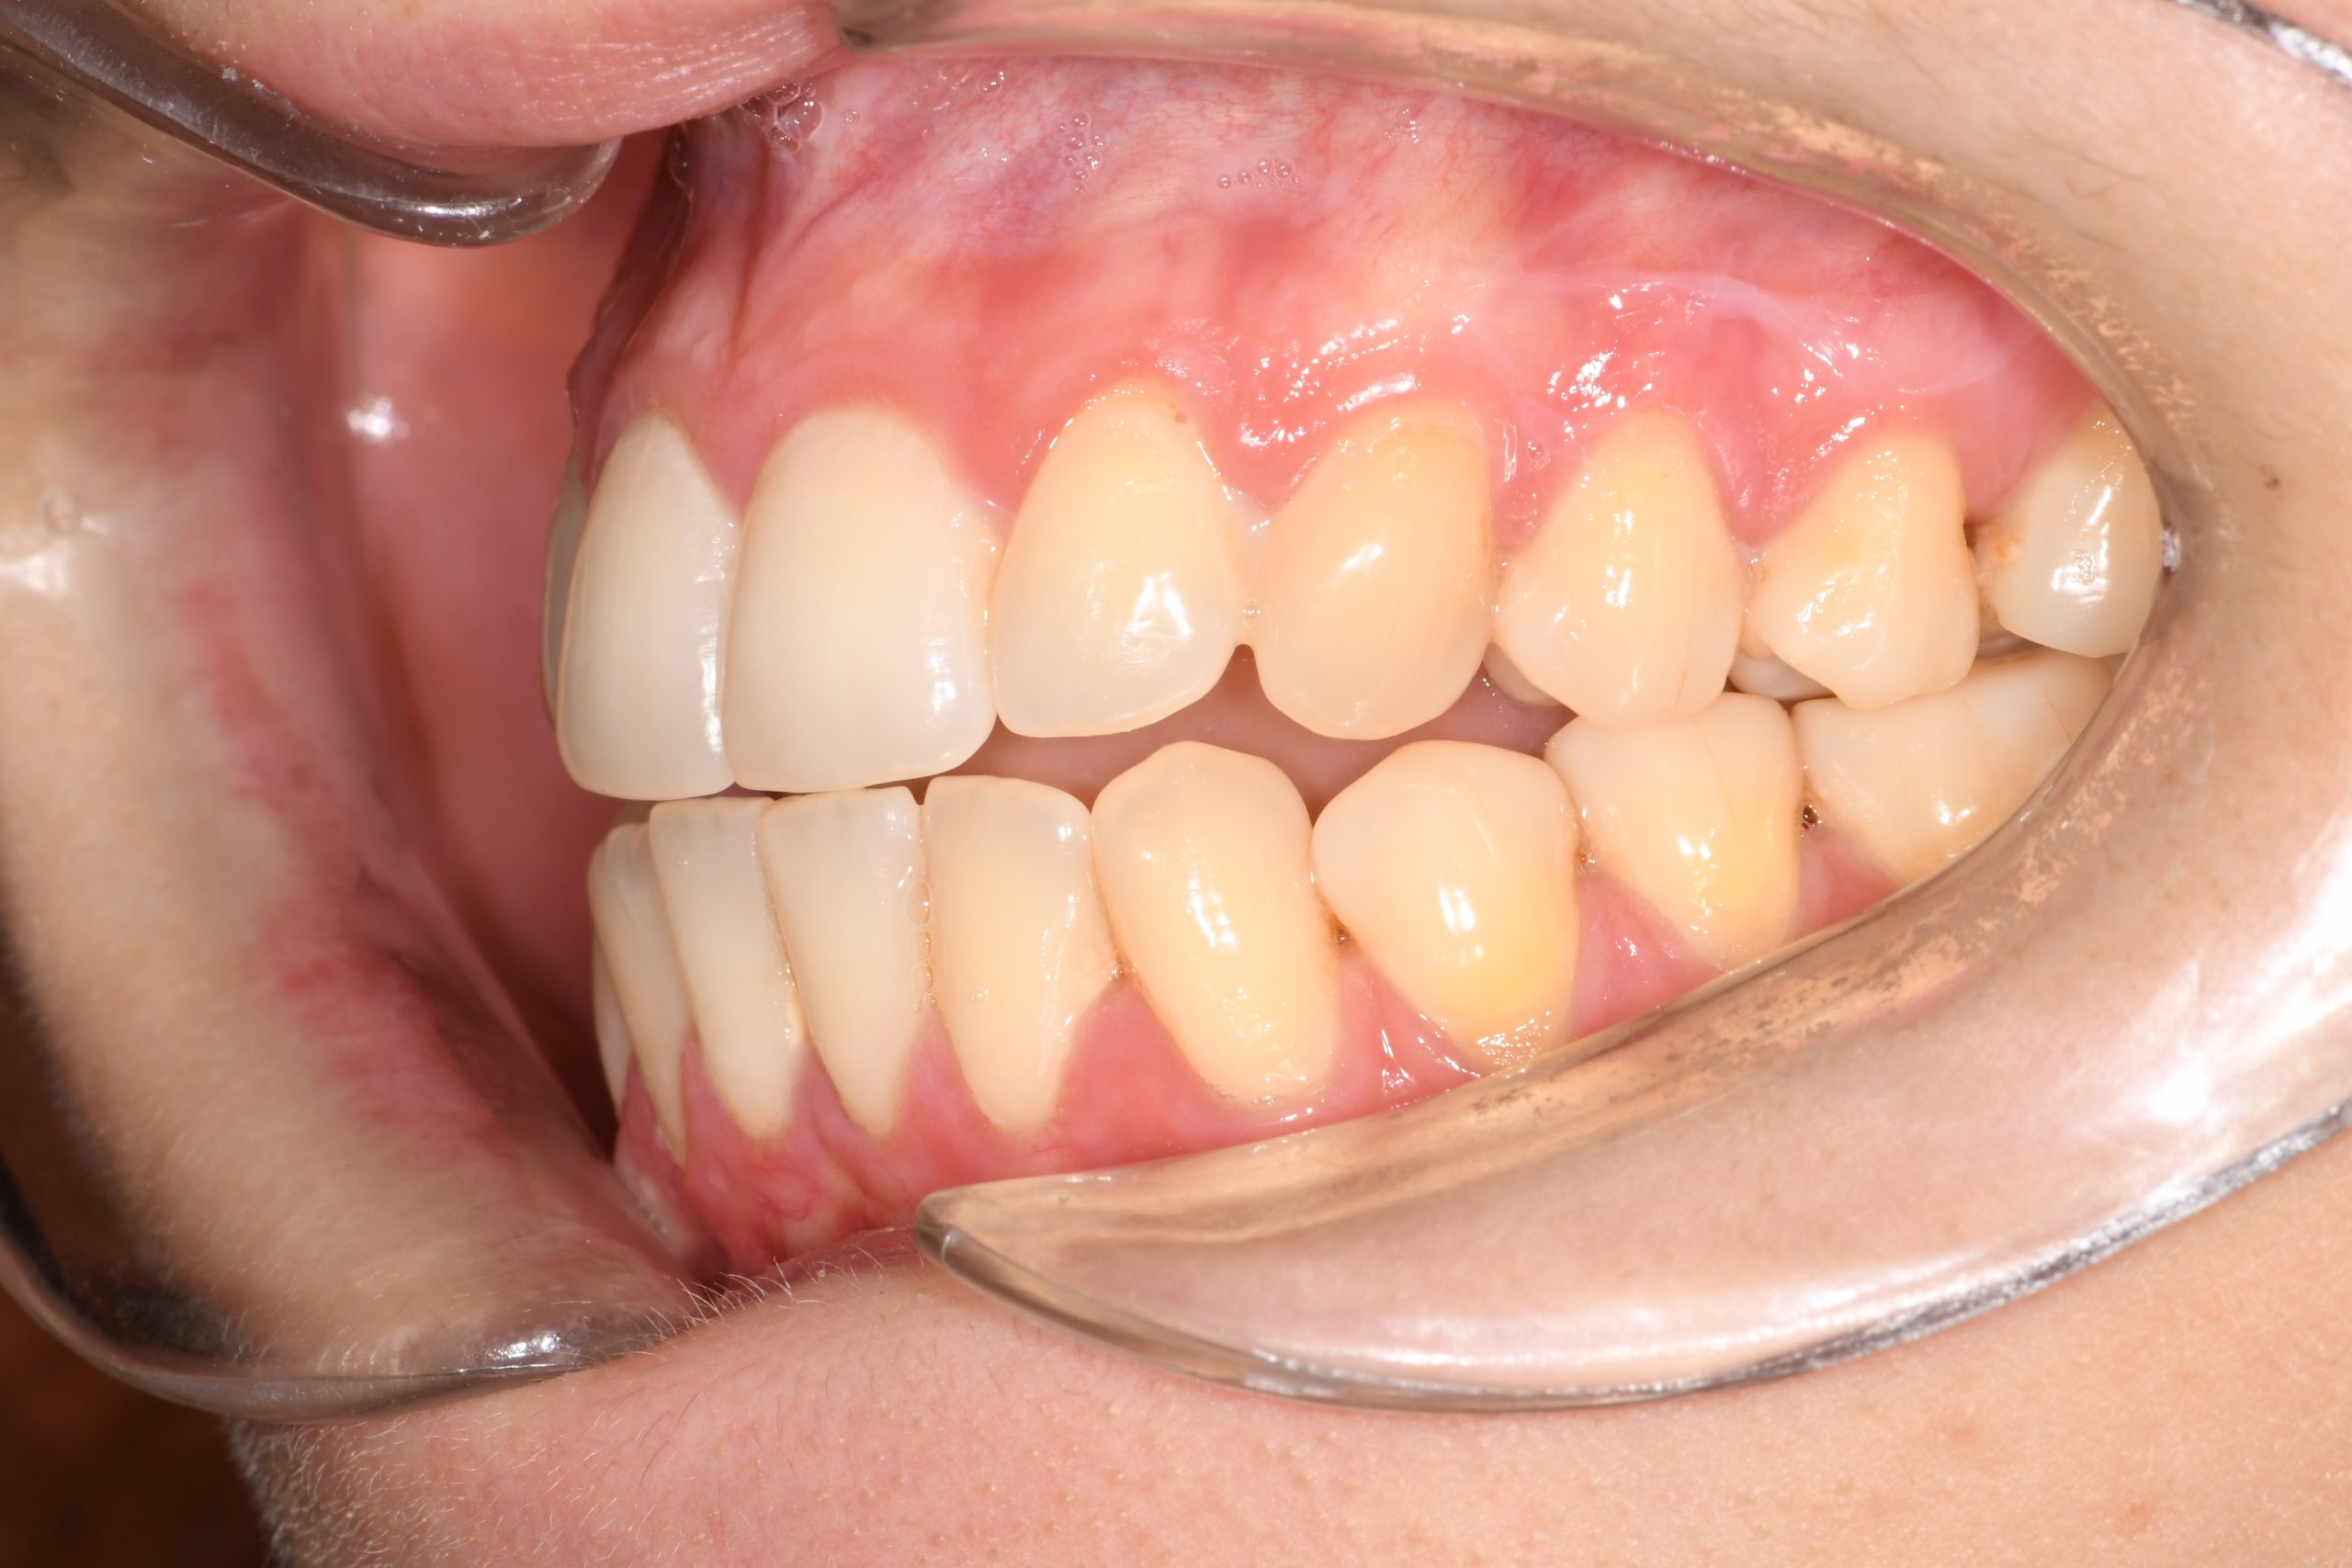

Az elmúlt évekből rengeteg szakmai referenciát tudnánk bemutatni, amelyek különböző fogszabályozási problémákat oldottak meg. Válogatva a több száz esetből, ezen az oldalon olyan képeket, információkat igyekeztünk bemutatni, amelyeknek a segítségével a jövőbeni pácienseinknek azt tudjuk üzenni: A Te fogsorod is lehet gyönyörű!

(Képeket a Pácienseink külön írásos beleegyezésével mutatjuk be!)